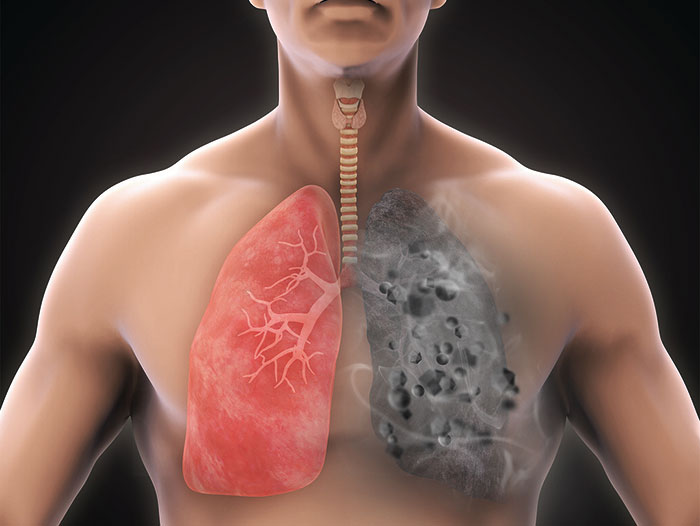

مواجهه با گرد و غبار میتواند تأثیرات کوتاهمدت و بلندمدتی بر سلامت تنفسی انسانها داشته باشد. برخی از این تأثیرات عبارتند از:

- افزایش خطر ابتلا به آسم و بیماریهای ریوی: افرادی که مستعد آسم یا بیماریهای مزمن ریوی (مانند COPD) هستند، در معرض گرد و غبار بیشتر با تشدید علائم خود مواجه میشوند. ذرات ریز میتوانند وارد ریهها شده و عملکرد آنها را مختل کنند.

- التهاب و عفونتهای تنفسی: در معرض گرد و غبار قرار گرفتن به مدت طولانی میتواند موجب التهاب مجاری تنفسی شود و در نهایت به بروز عفونتهای تنفسی کمک کند.